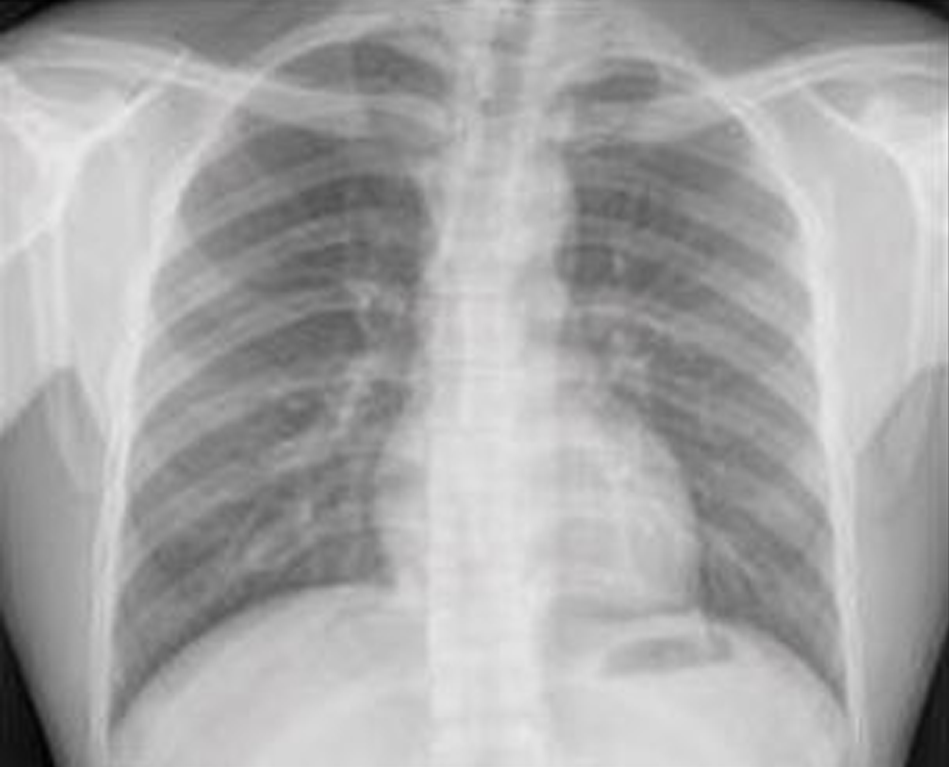

Researchers have developed a deep learning model that predicts the 10-year risk of major adverse cardiovascular events (MACE) from a single routine chest X-ray. The model had a similar performance to the established atherosclerotic cardiovascular disease (ASCVD) risk score, according to new study findings presented at the Radiological Society of North America (RSNA) 2022 Annual Meeting.

The researchers trained and developed a deep learning model, dubbed CXR-CVD risk, to predict the risk of death from cardiovascular disease from a single chest X-ray image. The model was trained using 147,497 chest X-rays from 40,643 participants from the Prostate, Lung, Colorectal, and Ovarian Cancer (PLOC) screening trial. The researchers tested the model using an independent cohort of 11,430 outpatients (mean age 60; 43% male) who had a routine chest X-ray and were potentially eligible for statin therapy. The prognostic value of CXR-CVD risk was compared to the established ASCVD risk score in a subset of 2,401 patients who had the aforementioned variables necessary to calculate ASCVD risk available in their electronic health records. The primary outcome was the observed 10- year incident of MACE (stroke and myocardial infarction).